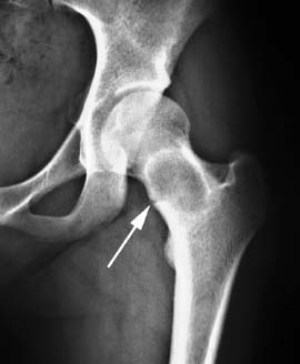

При рентгенологическом исследовании определяется крупный очаг до 20 см в диаметре, выходящий за пределы кости, но отграниченный надкостницей. Также определяются полости и разрушение костной ткани.

Диагноз основывается на клинических данных, рентгенологическом исследовании. Для уточнения характера новообразования проводят УЗИ, КТ, МРТ, ангиографию, пункционную трепанобиопсию пораженного участка, цитологический анализ внутриполостной жидкости.